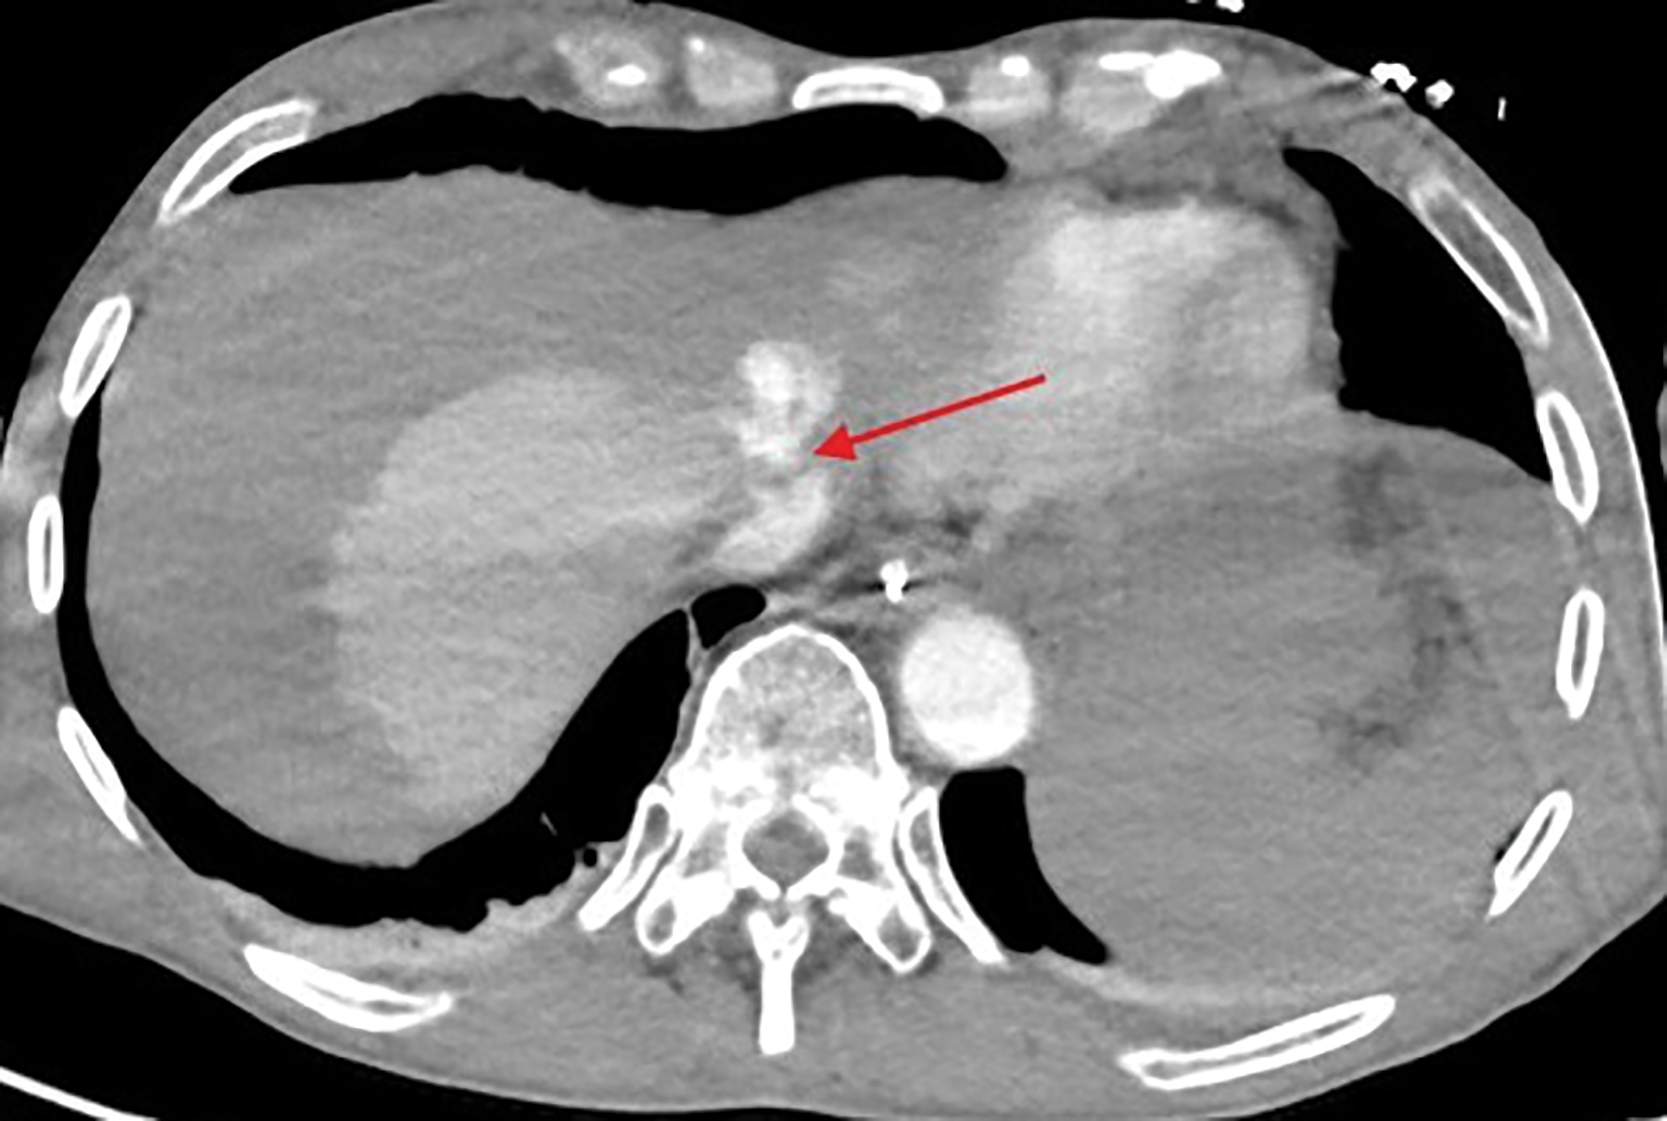

Figure 2

Lacerated left hepatic vein at the confluence with the vena cava.